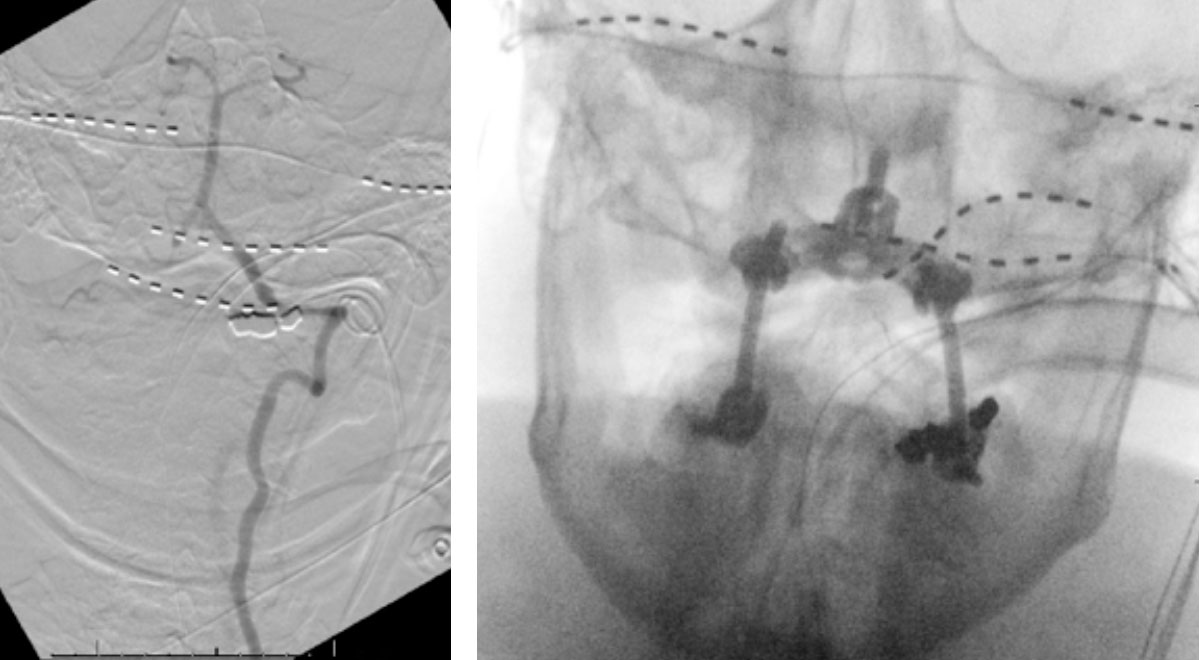

We performed conventional catheter angiography with provocative testing to reproduce his symptoms. The right Vertebral Artery is the codominant primary supply to the basilar circulation with reflux into the distal left Vertebral Artery that is occluded (Figure 3).

During neutral positioning, the vertebrobasilar circulation fills briskly from the Right Vertebral Artery. (Figure 4)